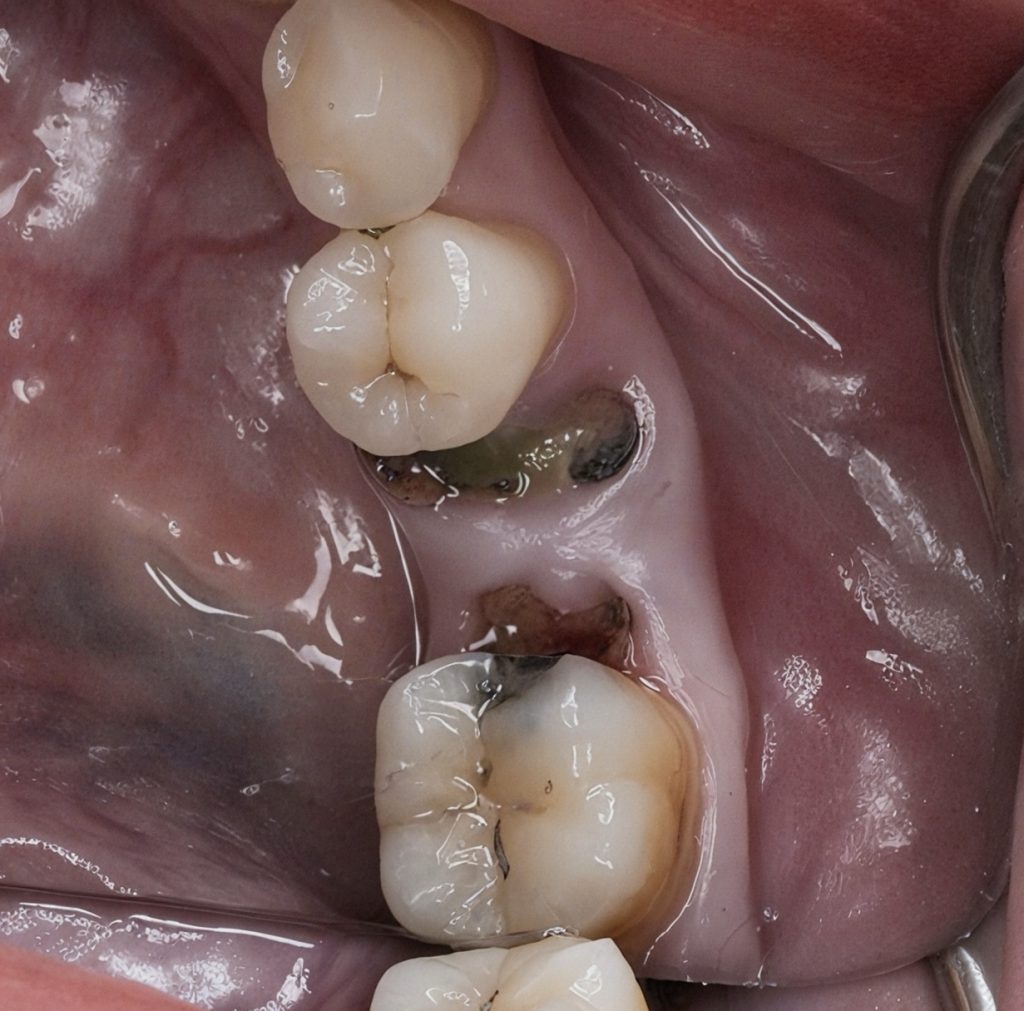

The patient presented with secondary caries beneath a failing distal composite and subgingival margin on the mandibular first molar. Adjacent premolar also exhibited proximal decay compromising contact and gingival contour (Fig 1–2). The objective was to perform a biologically respectful restoration preserving enamel and periodontal health.

Fig 1–2: Pre-operative clinical view showing extensive proximal caries and subgingival extension.